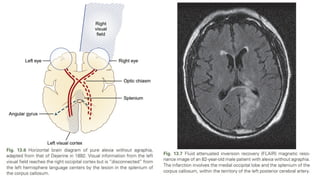

Pure Alexia Without Agraphia

Visual information from the left visual field

reaches the right occipital cortex but is

“disconnected” from the left hemisphere

language centers by the lesion in the splenium

of the corpus callosum.

• Patients can write but cannot read their own writing. They cannot read words at a glance, as

normal readers do.

• On bedside examination, speech, auditory comprehension, and repetition are normal.

• Naming may be deficient, especially for colors.

• Patients initially cannot read at all; as they recover, they learn to read letter by letter, spelling

out words laboriously.

• By contrast, they quickly understand words spelled orally to them, and they can spell normally.

• Associated deficits include a right hemianopia or right upper quadrant defect in nearly all

patients and, frequently, a deficit of shortterm memory.

• The causative lesion in pure alexia is nearly always a stroke in the

territory of the left posterior cerebral artery, with infarction of the

medial occipital lobe, often the splenium of the corpus callosum, and

often the medial temporal lobe.

• Dejerine postulated a disconnection between the intact right visual

cortex and left hemisphere language centers, particularly the angular

gyrus.

• Geschwind later rediscovered this disconnection hypothesis.

• Although Damasio and Damasio (1983) found splenial involvement in

only 2 of 16 cases, they postulated a disconnection within the deep

white matter of the left occipital lobe